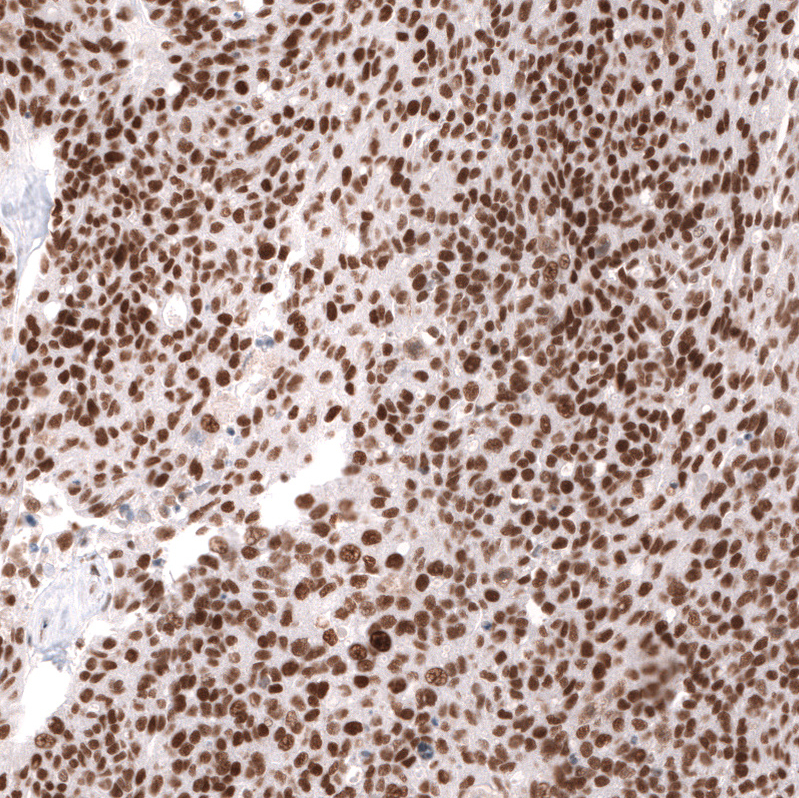

Immunohistochemical staining of human cerebral cortex shows strong nuclear positivity in neurons.